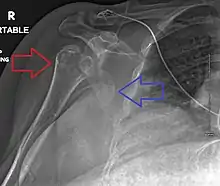

Definitive diagnosis of humerus fractures is typically made through radiographic imaging. For proximal fractures, X-rays can be taken from a scapular anteroposterior (AP) view, which takes an image of the front of the shoulder region from an angle, a scapular Y view, which takes an image of the back of the shoulder region from an angle, and an axillar lateral view, which has the patient lie on his or her back, lift the bottom half of the arm up to the side, and have an image taken of the axilla region underneath the shoulder.[9] Fractures of the humerus shaft are usually correctly identified with radiographic images taken from the AP and lateral viewpoints.[12] Damage to the radial nerve from a shaft fracture can be identified by an inability to bend the hand backwards or by decreased sensation in the back of the hand.[5] Images of the distal region are often of poor quality due to the patient being unable to extend the elbow because of pain. If a severe distal fracture is suspected, then a computed tomography (CT) scan can provide greater detail of the fracture. Nondisplaced distal fractures may not be directly visible; they may only be visible due to fat being displaced because of internal bleeding in the elbow.[7]